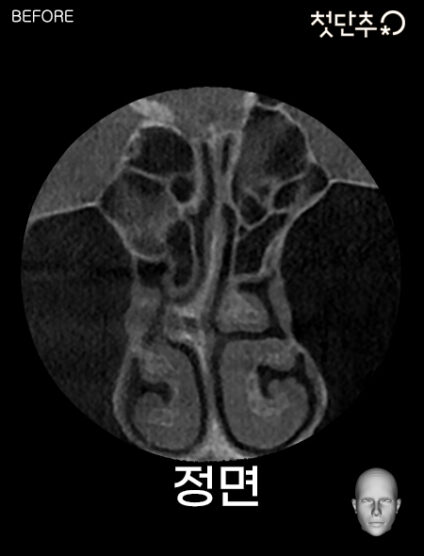

기능코성형이란? 코막힘, 비염 등의 코의 기능적 문제와 미용적인 코의 모양을 함께 개선하는 수술입니다.

코막힘은 여러 합병증을 유발하기 때문에 초기에 치료하는 것이 중요합니다. 다양한 원인으로 발생하는 비염수술은 이비인후과 전문의의 진단과 수술이 꼭 필요합니다.

비중격 교정술 시 채취되는 비중격 연골은 코성형의 좋은 재료입니다.

코성형만 한 후에 나중에 코막힘으로 인해 비중격 교정술을 받아야 하는 경우나 이미 시행한 코성형으로 비중격교정술의 난도가 매우 높아질 수 있습니다. 코성형이나 기능적 개선을 원한다면 동시에 수술을 하는 것이 유리합니다.